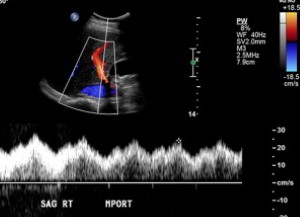

Siêu âm là phương tiện chẩn đoán hình ảnh nhậy để phát hiện khí trong tĩnh mạch cửa. Trên siêu âm thang xám, khí trong tĩnh mạch cửa biểu hiện là các chấm âm sáng, nhỏ chuyển động nhanh trong các nhánh tĩnh mạch (Hình 8). Trên siêu âm Doppler, các nhiễu ảnh tần số cao, giống như gai chồng vào sóng tĩnh mạch cửa là dấu hệu đặc trưng của khí trong tĩnh mạch (Hình 9) [16].

Hình 9. Khí trong tĩnh mạch cửa ở bệnh nhân nữ 53 tuổi sau ghép gan. Ảnh siêu âm Doppler màu gan ghép cho thấy các nhiễu ảnh tần số cao, giống như gai (mũi tên) chồng lên sóng tĩnh mạch cửa.